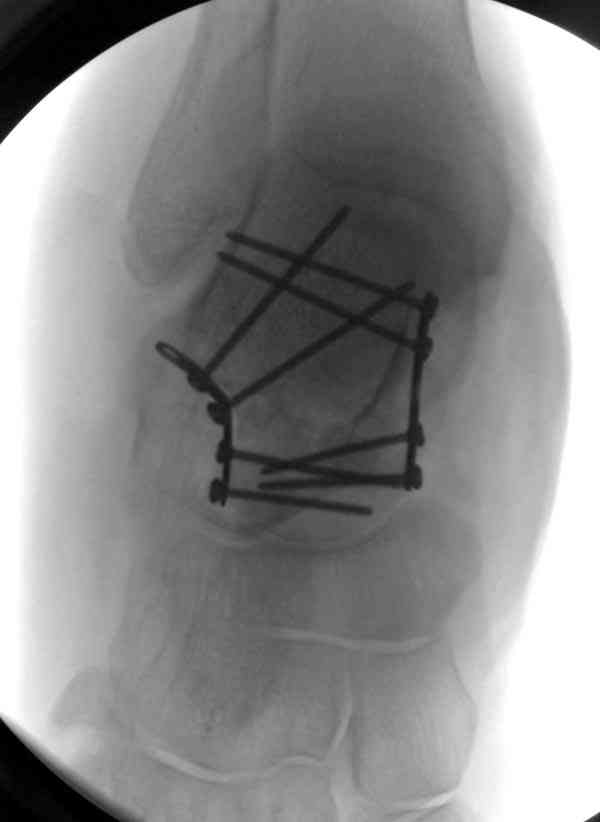

И второй случай из недавней ташкентской практики, (извините за качество ренгенограммы и только в одной проекции) случай падения с высоты (кстати моего друга - известного киноактера) - открытый

смещенный перелом тарана, с переломом переднего края дистального эпиметафиза большеберцовой кости.

При поступлении в приемной сделана первичная обработка с ушиванием открытой латеральной раны и вытяжением за пятку.

Из-за отсутствия времени пришлось оперировать на второе утро, из материала, что имеем на месте, фиксирован двумя шурупами, а третий-это контур сломанного жойстика в 4 мм. На дистальный медиальный конец тибиа antiglide 3.5 мм пластина. Через пару дней выписан и несмотря на предупреждение, самостоятельно начал нагрузку в 4 недели, время не ждет, снимается в боевике в Росийской Федерации.